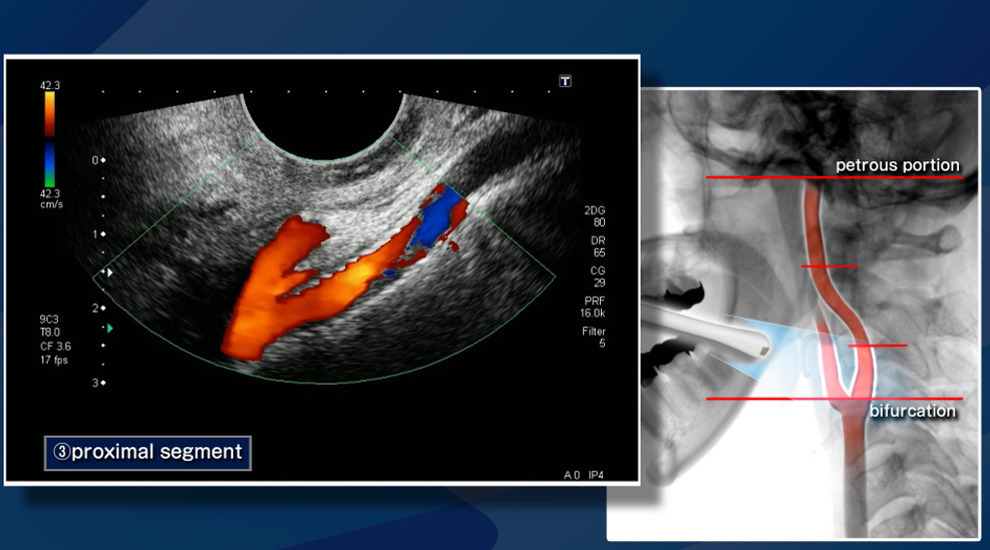

경동맥 초음파(Carotid Ultrasound)는 목 양쪽에 위치한 경동맥(carotid artery)의 혈류 상태를 확인하는 비침습적 영상 진단법입니다. 경동맥은 뇌로 혈액을 공급하는 주요 동맥으로, 이 부위에 죽상경화(동맥경화)가 발생하면 뇌졸중(중풍)이나 일과성 허혈 발작(TIA) 등 치명적인 뇌혈관 질환으로 이어질 수 있습니다.

이 검사는 초음파를 통해 경동맥 내벽의 두께, 혈류 속도, 혈전이나 협착(좁아진 부분) 여부 등을 정밀하게 경동맥 초음파 검사로 알 수 있는 병들을 관찰하여, 뇌졸중 위험성을 사전에 파악할 수 있는 중요한 예방 의료 행위입니다.

- 초음파 검사 시행

- 침대에 누워 목 양쪽에 초음파 탐촉자(probe)를 대고 관찰